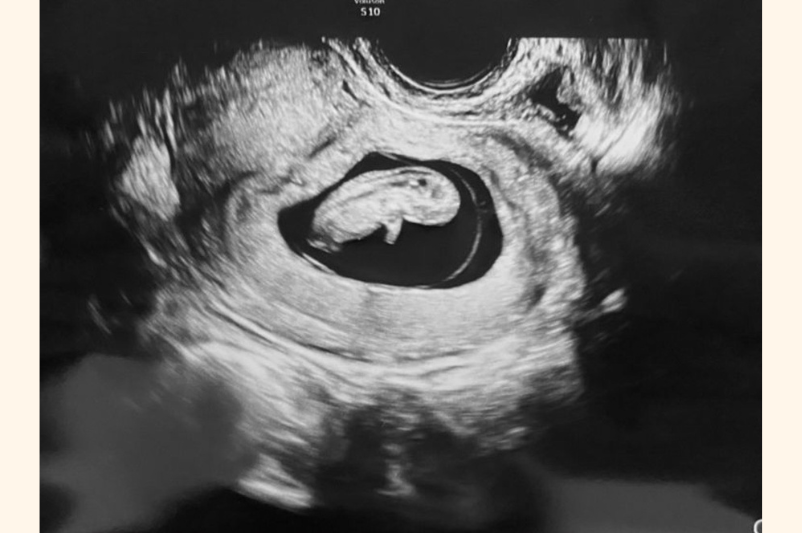

3度めの妊娠で「9週の壁」を乗り越えた!

薬が効く保証はないし、またダメだったらどうしよう…と、常に不安はありました。けれど、3度めの妊娠では初期流産することもなく、無事に「妊娠9週の壁」を乗り越えることができたんです!

おなかの中ですくすく成長してくれました!

過去に2回、流産というつらい経験をしたので、妊婦検診で「順調です」と言われるたびに診察室で泣いてしまい、看護師さんに「大丈夫だよ」と励まされた妊娠期間でした。